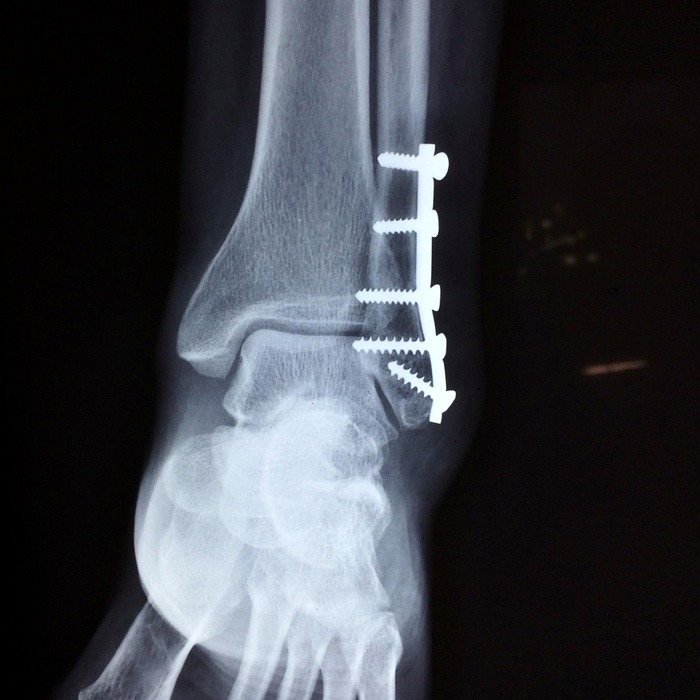

X-레이

X-레이 검사는 인대 손상을 직접적으로 볼 수는 없지만, 골절이나 뼈의 변형 여부를 확인하는 데 유용합니다. 무릎 주변의 뼈 환경을 확인하여 다른 가능한 부상 방법을 식별할 수 있습니다.